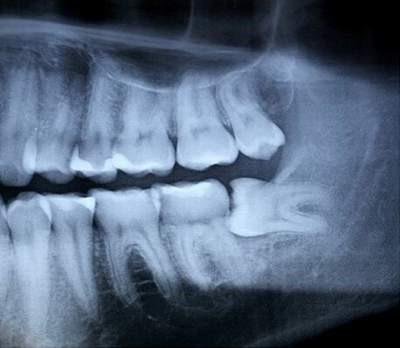

Khi răng không mọc thẳng, đầy đủ trong miệng mà nằm nghiêng lệch hay ở bên trong xương hàm thì được gọi là răng bị lệch, ngầm (impacted tooth). Nói chung, răng lệch, ngầm thường là những răng không thể tách xuyên qua nướu được vì không có đủ chỗ mọc. Số người có răng lệch ngầm trong dân số là khá cao với tỉ lệ gần 90%.

Răng khôn lệch, ngầm có thể làm hư hại răng bên cạnh, hoặc gây ra sâu răng, viêm nha chu, nhiễm trùng xương hàm, cứng khít hàm, vv. Nguyên nhân là do vùng răng này khó làm sạch, vì vậy sẽ thu hút vi khuẩn đến gây ra các bệnh về răng và nướu. Vi khuẩn vùng miệng có thể đi từ miệng vào máu. Tại đây có thể dẫn đến nhiễm trùng toàn thân và các bệnh có ảnh hưởng đến tim, thận, các cơ quan khác. Tuy nhiên, tình trạng này có thể cải thiện sau khi nhổ răng này đi.

Trong một số trường hợp u nang chứa đầy dịch hoặc các khối u có thể được hình thành trên nền các răng khôn không được điều trị. U nang phát triển có thể dẫn đến các vấn đề nghiêm trọng hơn vì chúng tạo hốc trống trong xương hàm, phá hoại dây thần kinh răng dưới, răng xung quanh và các cấu trúc khác.

Răng khôn mọc hoàn toàn, có chức năng, không đau, không sâu, được giữ vệ sinh tốt, mô nướu khỏe mạnh, không bệnh lý có thể không cần nhổ. Tuy nhiên, chúng cần được kiểm tra định kì, làm sạch ở phòng khám, kiểm tra bằng phim X-quang quanh chóp để kiểm soát bất kì thay đổi bất thường nào.